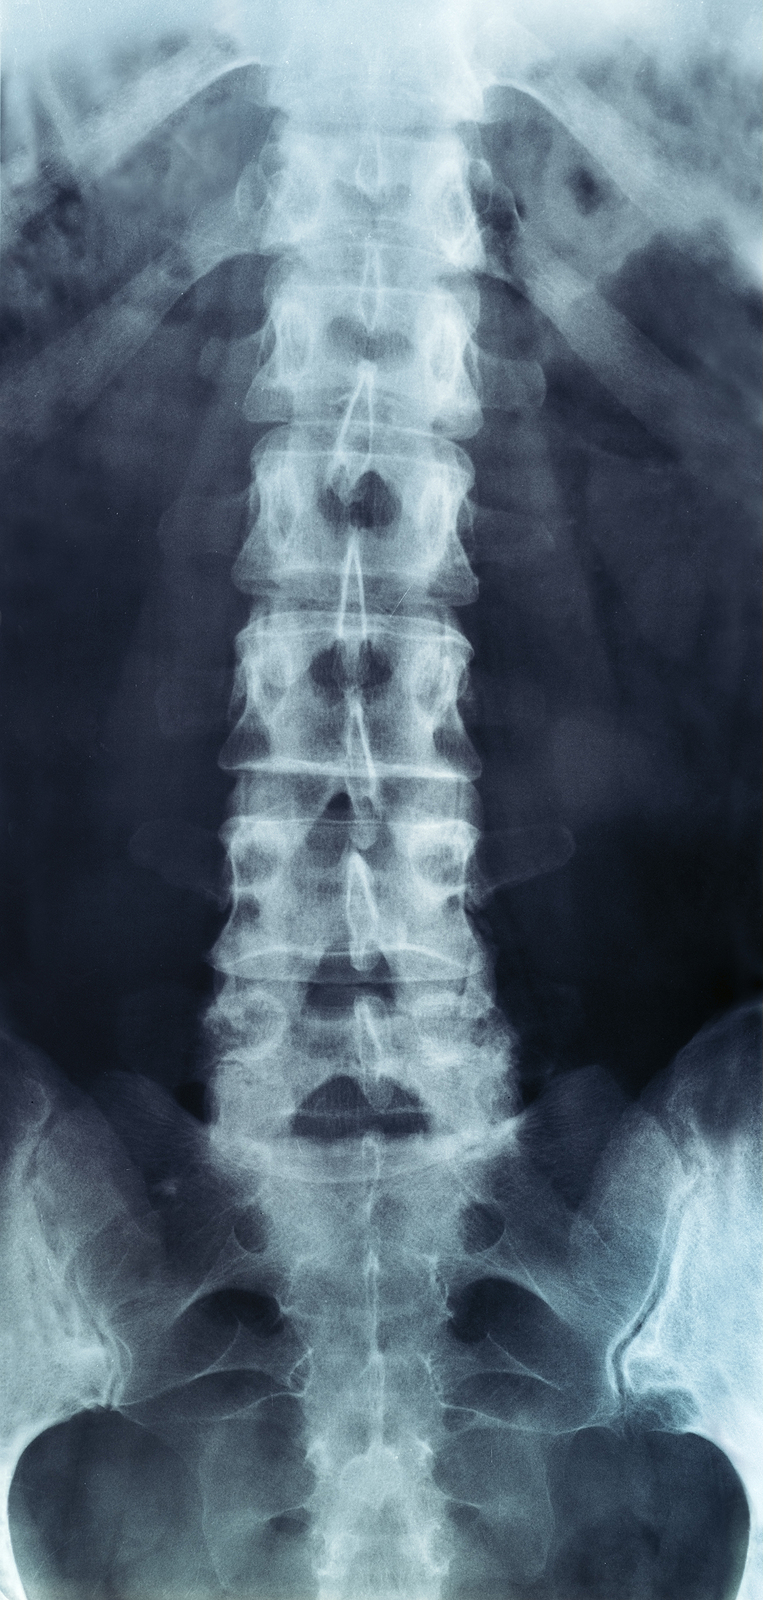

The human spine is made up of 24 spinal bones, called vertebrae, as well as the sacrum and the coccyx. The sacrum is a triangular bone near the bottom of the spine and the coccyx is more commonly known as the tailbone.

Vertebrae are stacked on top of one another to create the spinal column. The spinal column gives the body its form and helps sustain an upright position.

The lumbar spine—where pain is often experienced—is made up of five vertebrae positioned near the bottom of the spinal column. Doctors often refer to these vertebrae as levels L1, L2, L3, L4 and L5. The ‘L’ refers to ‘lumbar’. The lowest vertebra, L5, is connected to the top of the sacrum—a triangular bone at the base of the spine that is located between the two pelvic bones. Some people are born with an extra or sixth lumbar vertebra called L6. Having an extra vertebra doesn't usually cause physical problems.

X-rays

X-rays are usually the first test ordered before any of the more specialized tests are completed. X-rays use electromagnetic radiation to show problems with bones and can also reveal problems such as fractures, infections, or bone tumors. X-rays of the spine can give your doctor information about bone alignment and can demonstrate how much degeneration has occurred in the spine. Both alignment and degeneration can affect the amount of space in the neural foramina and between the discs, which subsequently impacts the nerves in the area. This is important information your health care professional can use to establish a treatment plan.

Flexion and Extension X-rays

Special x-rays called flexion and extension x-rays may help to determine if there is true instability between vertebrae. These x-rays are taken from the side as you bend as far forward and then as far backward as you can. Comparing the two x-rays allows the doctor to see how much motion occurs between each spinal segment.